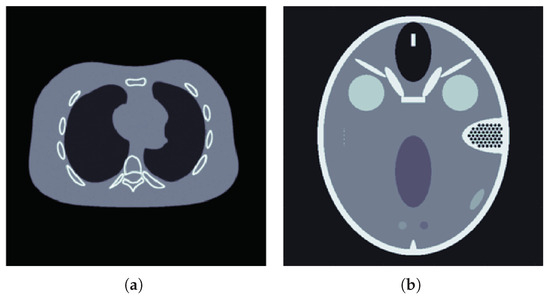

4. Numerical Experiments

4.2. Results for Limited View Data

4.3. Results for Sparse View Data